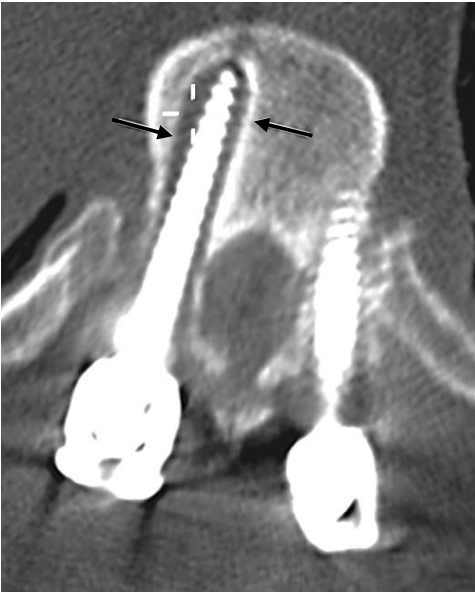

Assinale a alternativa que corresponde a complicação pós operatória na imagem abaixo.